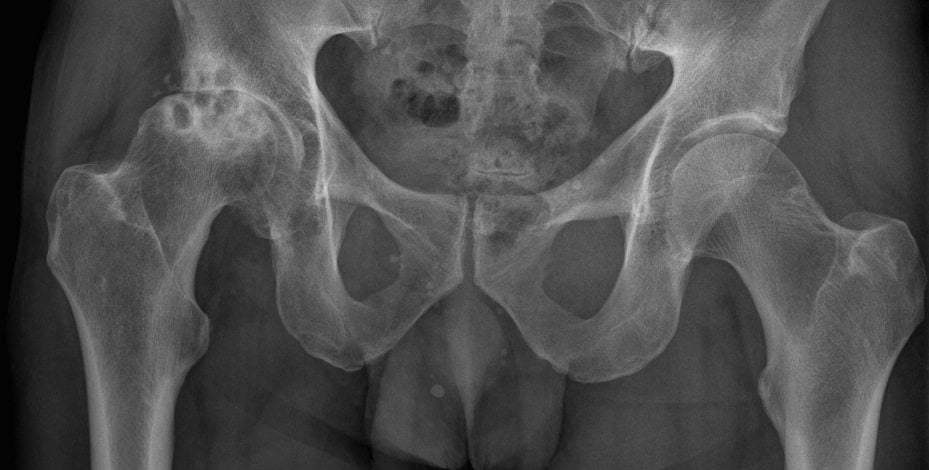

Признаки остеоартроза сустава 3 степени:

- сильный хруст в суставе, который развивается во время движения (от трения костей);

- постоянные сильные боли, которые очень сложно купировать обычными анальгетиками;

- болезненная пальпация;

- значительная деформация;

- активный воспалительный процесс;

- потеря возможности передвигаться без трости или костылей.

При переходе заболевания в 3 степень протекания у человека в разы повышается риск развития опасных осложнений. В таком состоянии нужно как можно скорее начинать комплексное лечение.